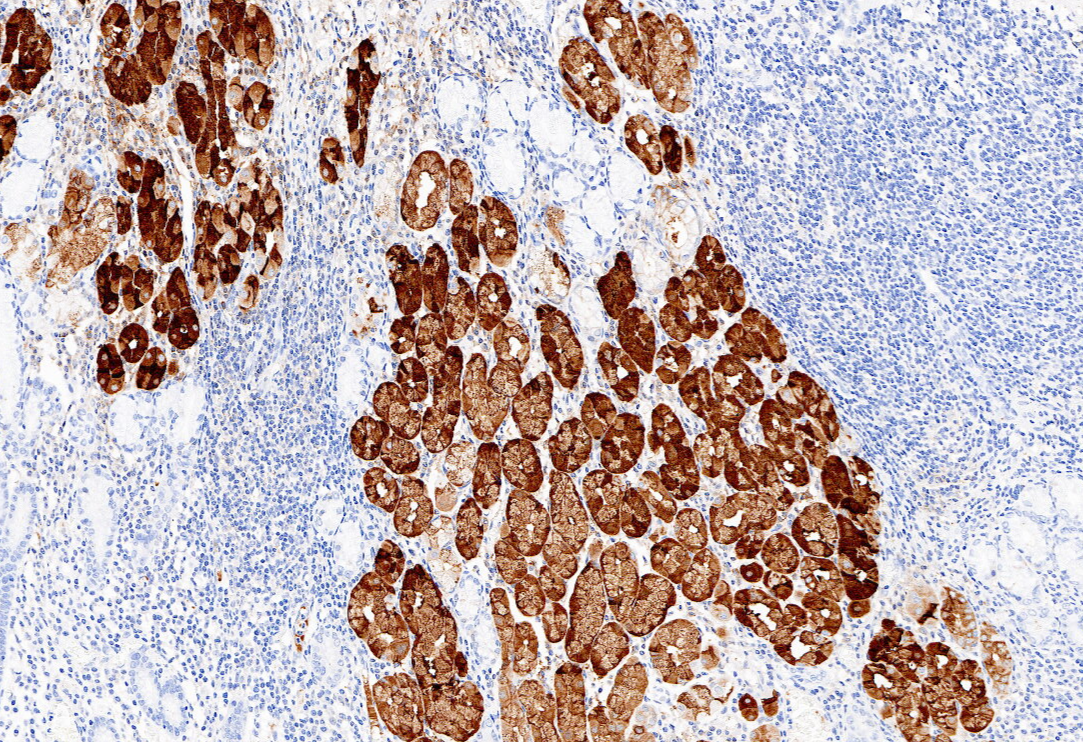

【新品单抗】Pepsinogen I

胃蛋白酶原Ⅰ(PepsinogenⅠ)主要由胃底腺的主细胞和黏液颈细胞分泌,当胃黏膜发生萎缩时,主细胞数量减少,Pepsinogen Ⅰ分泌减少。因此,Pepsinogen Ⅰ可在一定程度上反映胃黏膜的分泌功能和病理状态,在胃癌及慢性萎缩性胃炎的诊断中具有重要的临床意义。

| 克隆号 | 定位 | 阳性对照 | 修复条件 |

| 7G3 | 细胞浆 | 胃 | 高PH热修复 |

胃石蜡组织,用Pepsinogen I染色,DAB显色